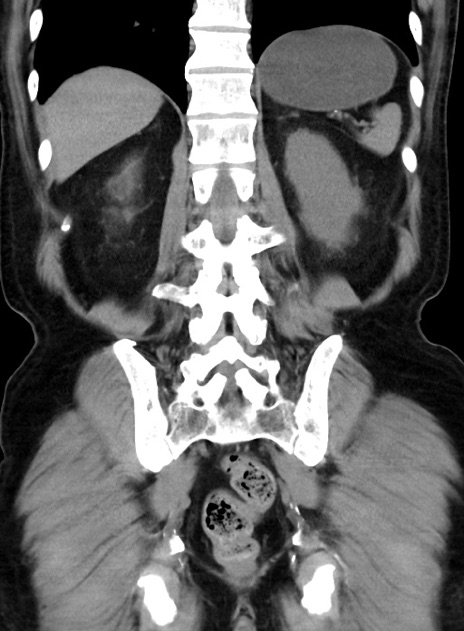

横断像

【症例】70歳代 男性

【主訴】腹痛・嘔吐

【現病歴】昨晩より、嘔吐・腹痛あり。今朝になっても嘔吐あり。来院。

【既往歴】心臓バイパス手術、開腹胆摘、腸閉塞

【身体所見】BP 107/71mmHg、HR 116/min、腹部:平坦、軟、下腹部に軽度圧痛あり。反跳痛なし。

【データ】WBC 15100、CRP 0.32